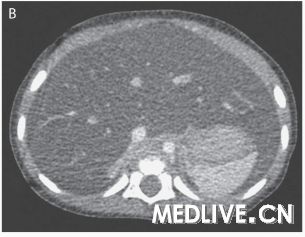

图1 腹部成像检查 右肝叶矢状面超声图像(图A)显示,与邻近的肾脏相比,肝实质回声增强,这与脂肪浸润(的表现)一致。腹部轴向计算机体层摄影图像(图B)显示,弥漫性肝脏密度降低,这也与脂肪浸润(的表现)一致。

奥托·拉帕利诺医师:入院时进行的腹部超声显示肝实质回声弥漫性增强,符合脂肪浸润,没有局灶异常,并且胆囊周围有少量液体(图1A)。为了进一步评估肝脏而进行的腹部CT检查显示,肝实质脂肪性衰减,轻度肝肿大,以及胆囊周围有少量液体(图1B)。